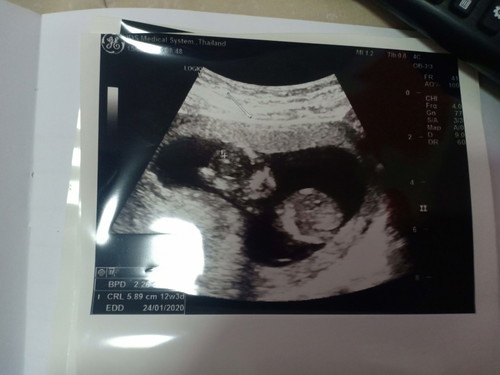

ของเรา 12 วีค กับ3วัน ตอนนี้ 13 วีคกับ4วัน แล้วค่ะ

ตอนซาว 12 วีค ตอนนี้ 13วีค แล้วจ้า